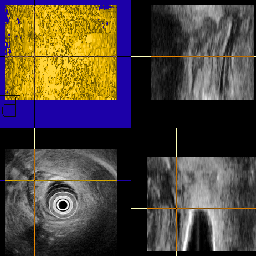

Mini-probe intra-luminal study of bile ducts within the liver.

Fig. 1.

A bile duct - MPR View.